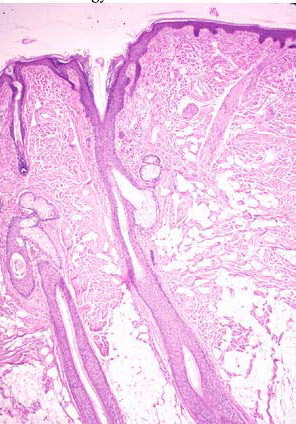

Hair Bulb = بصلة الشعرة